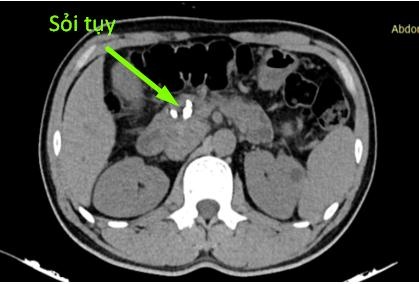

Người bệnh P.T.N. vào viện với thể trạng gầy, da niêm mạc vàng đậm, đau nhiều thượng vị lan sau lưng, ăn uống kém. Trên phim cộng hưởng từ và cắt lớp vi tính cùng với siêu âm nội soi (2 lần) đều cho thấy có hình ảnh giãn ống tụy, sỏi tụy, giãn đường mật trong và ngoài gan, không rõ khối vùng đầu tụy.

Hình ảnh sỏi tụy trên CLVT của bệnh nhân. Ảnh: BVCC.

Phim chụp cắt lớp vi tính cho thấy hình ảnh nhu mô tụy teo nhỏ, ống tụy giãn 1 cm và trong có rất nhiều sỏi. Người bệnh được chẩn đoán sỏi tụy/viêm tụy mạn - nghiện rượu và chỉ định phẫu thuật theo phương pháp Frey.